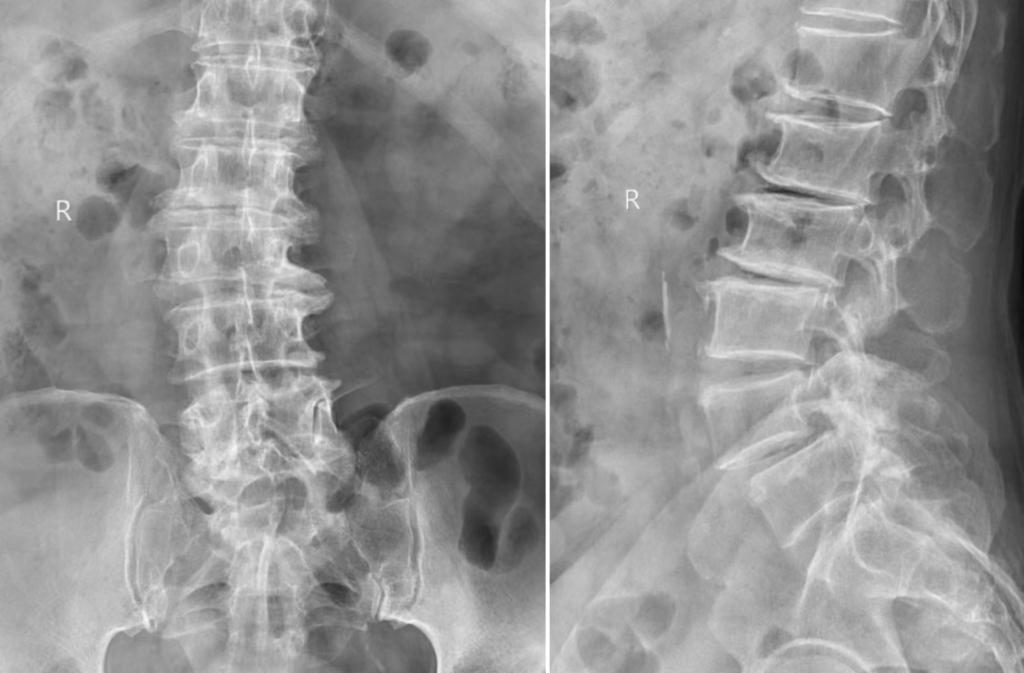

术前腰椎X线片和MRI

73岁的男性患者因“长期腰痛伴双下肢无力10余年”就诊于我医院运动医学科脊柱微创门诊。经过详细检查和评估后发现其存在腰3~骶1(L3-S1)多节段椎间盘突出、腰椎滑脱、椎管狭窄,退变性侧弯等问题,面对如此复杂的病情,柏传毅教授决定采用多窗口经肌间隙入路技术进行微创手术治疗,同时完成椎间盘减压,椎间隙固定融合,腰椎不稳定及侧凸矫形。在小通道多窗口经多个肌间隙,分别对3个节段病变椎间盘减压,椎间隙融合固定,并对脊柱的侧弯和滑脱矫形,充分体现了微创手术效果好、创伤小、康复快的特点。较以往观念,多节段脊柱无法做微创的观念,在熟练掌握传统微创技术下提出了多窗口经肌间隙入路技术,可以完成3节段及以上的椎间盘减压,椎间隙固定融合,脊柱不稳定及侧凸矫形等手术,对于高龄患者,多节段腰椎疾病及现在血源短缺的医疗环境下相对于传统手术有很大的优势。